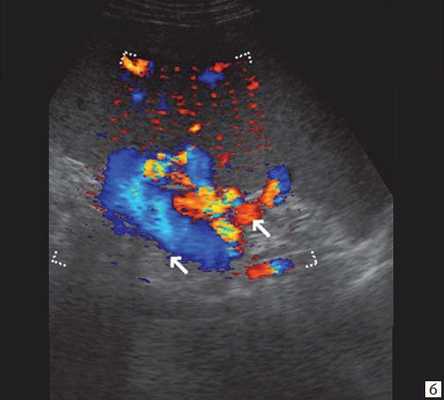

• Цветовая допплерография:

о Позволяют достоверно дифференцировать расширенные протоки (в которых отсутствуют признаки кровотока) от прилегающих сосудистых ветвей печеночной артерии и воротной вены

(Правый) При цветовой допплерографии у того же пациента отмечается отсутствие кровотока в расширенных тубулярных структурах, что указывает на то, что это и в самом деле расширенные желчные протоки. Следует выполнять цветовую допплерографию в повседневной практике для подтверждения дилатации желчных протоков.

(Левый) При цветовой допплерографии на поперечном УЗ срезе печени наблюдается легкое расширение внутрипеченочных желчных протоков их диаметр немного превышает два миллиметра. Причиной легкой дилатации желчных протоков стала обтурация конкрементом (не показан).

(Правый) При цветовой допплерографии на поперечном УЗ срезе печени наблюдается небольшое расширение внутрипеченочных и внепеченочных протоков. У пациента был диагностирован стеноз ампулы в сочетании с холангитом, которые стали причиной дилатации желчных протоков.